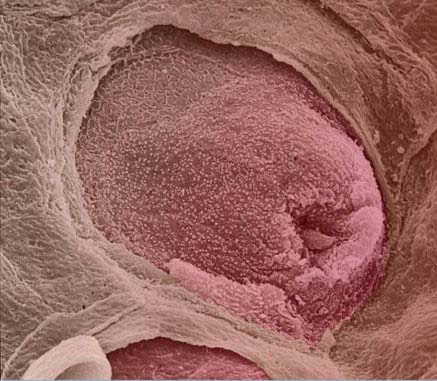

سلولهای بنیادی مغز استخوان انسان